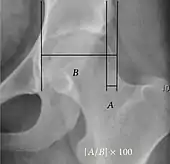

Reimer's migration index[9] | ![]() |

The percentage of the femoral head that lies outside of the acetabular roof. It is also called the femoral extrusion index. | <25% |